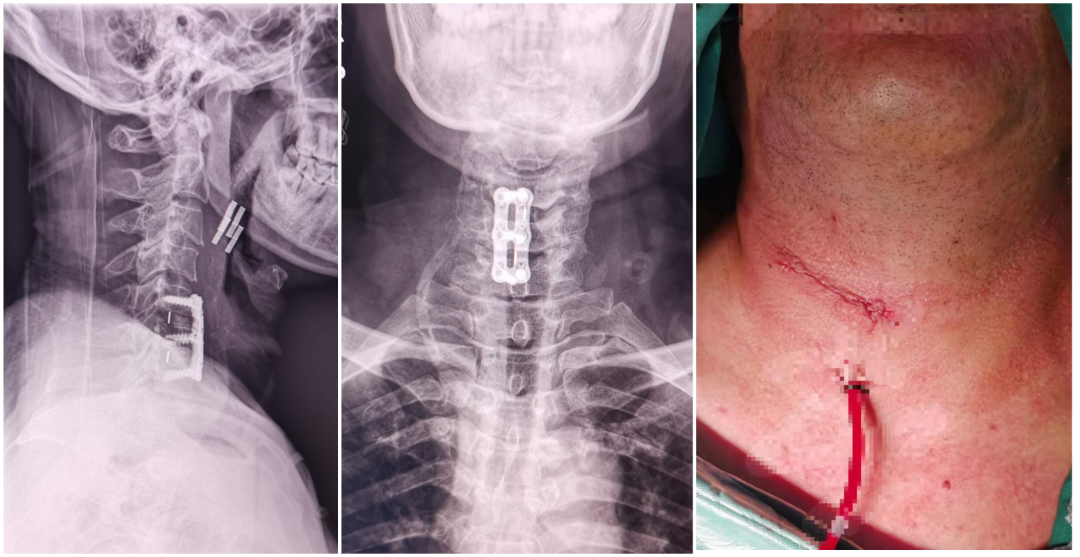

患者叶某,22岁男性,2月前劳动后出现腰部酸胀、麻痛,弯腰困难,站立行走、下蹲时明显,疼痛可向右大腿及小腿后侧及足底放射,平躺休息后缓解,症状反反复复,双下肢肌力感觉基本正常,结合辅助检查,诊断:腰5/骶1椎间盘突出,于局麻下行椎间孔镜下腰5/骶1椎间盘髓核摘除+神经根松解术,术后患者腰背部、右下肢无明显疼痛,术后第一天佩戴腰围下床自由活动。

术前CT、MR示:腰5/骶1巨大椎间盘突出

术后复查CT示:椎间盘已完全摘除

术后切口:7mm小切口